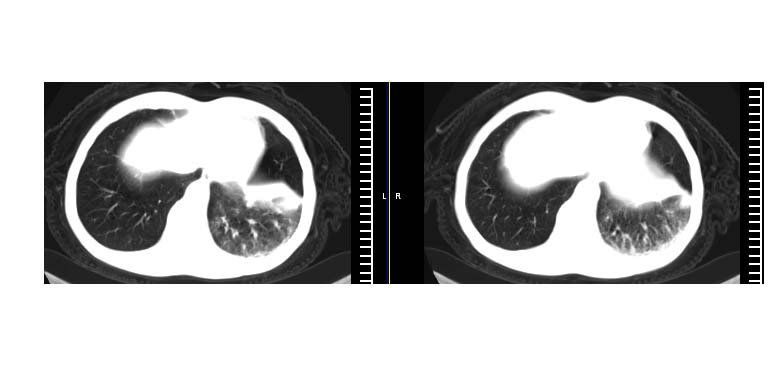

标题: CT11019:男性,66岁。发烧5-6天。治疗后无明显好转。 [打印本页]

标题: CT11019:男性,66岁。发烧5-6天。治疗后无明显好转。

左侧胸廓偏小,左下梭形高密度影,考虑阻塞性肺炎.

斜肋积液

斜裂积液,炎症

明明是斜裂胸膜积液,为何都考虑阻塞性肺炎、肺不张(边缘内凹,而本例是外凸)。